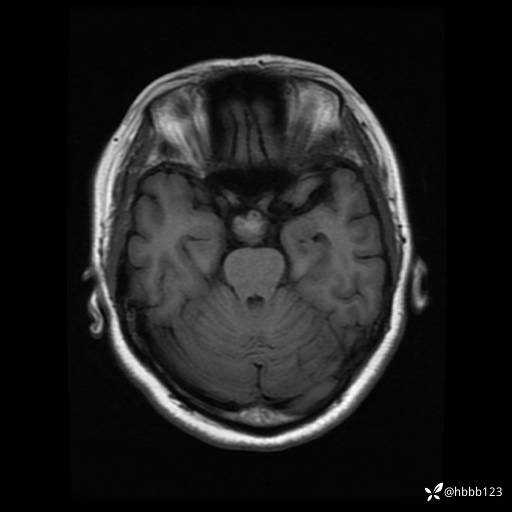

T1WI: